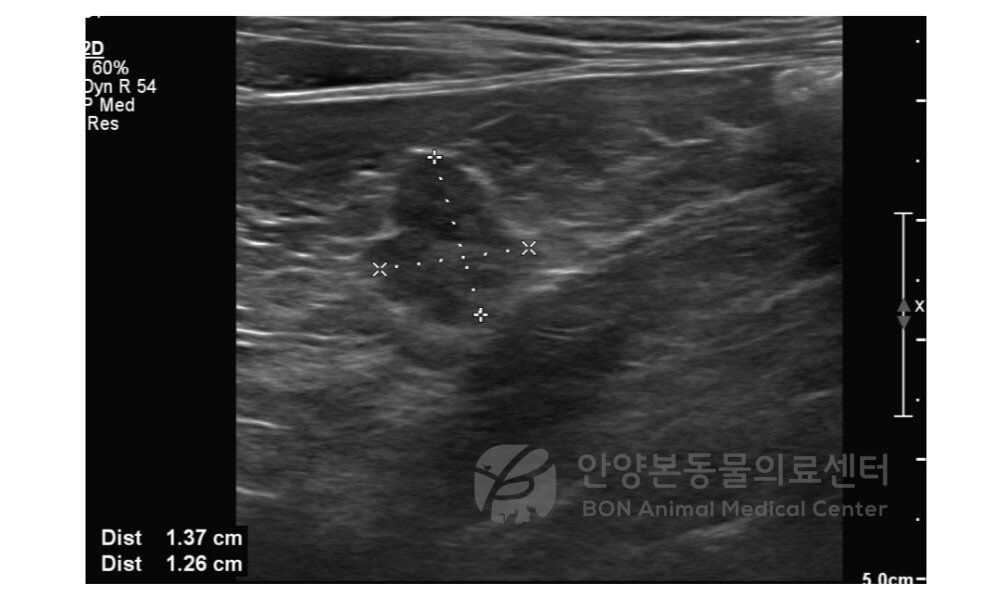

본문 이미지 - 인슐린종이 진단된 고양이의 복부 초음파 영상(본동물의료센터 제공) ⓒ 뉴스1

인슐린종이 진단된 고양이의 복부 초음파 영상(본동물의료센터 제공) ⓒ 뉴스1